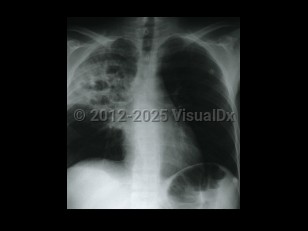

Chest pain, Pleural effusion, 50-59 year old Female

Lung cancerLung cancer

TuberculosisTuberculosis

Lung abscess